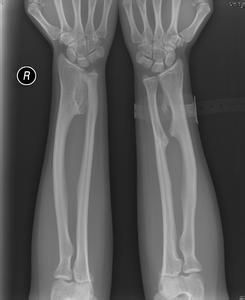

男性多見,有顯著的家族遺傳病史。所有的軟骨內化骨的骨骼均可發病,其中以四肢長管骨的乾骺端最多見。常對稱性發生,下肢發病多於上肢,下肢以膝關節周圍骨骼最多。早期腫瘤小常無症狀,一般在兒童和青春期由於骨贅增生成腫塊、發生畸形、壓迫附近軟組織而疼痛時方被注意而發現。腫瘤在關節附近可影響關節功能,壓迫神徑時(特別是腓總神經)可引起相應的症狀。多發性骨軟骨瘤病在兒童早期就可發現,到青少年時,前臂可發生弓形畸形,手向尺側偏斜,有時可有骨盆和胸廓變形。2、影像學多發性骨軟骨瘤的表現

X線表現與孤立性骨軟骨瘤相似,僅在許多骨上有不同大小的骨軟骨瘤。膝部附近的骨胳,如股骨下端、脛骨下端、腓骨上端有大小不等的骨軟骨瘤甚至膝關節上下可因骨軟骨瘤的生長而交鎖,甚至類似骨融合,除長管狀骨外,肩胛骨的脊椎緣也是常見的好發部位,然後依次為有掌骨、跖骨、指骨、趾骨、肋骨、脊椎和骨盆。髂骨嵴在與骺軟骨的連線處,可有無數的小骨軟骨瘤出現。顱骨從未發生過這種病損。發生惡性變後ECT表現惡變部位代謝明顯活躍。3、多發性骨軟骨瘤的病理表現